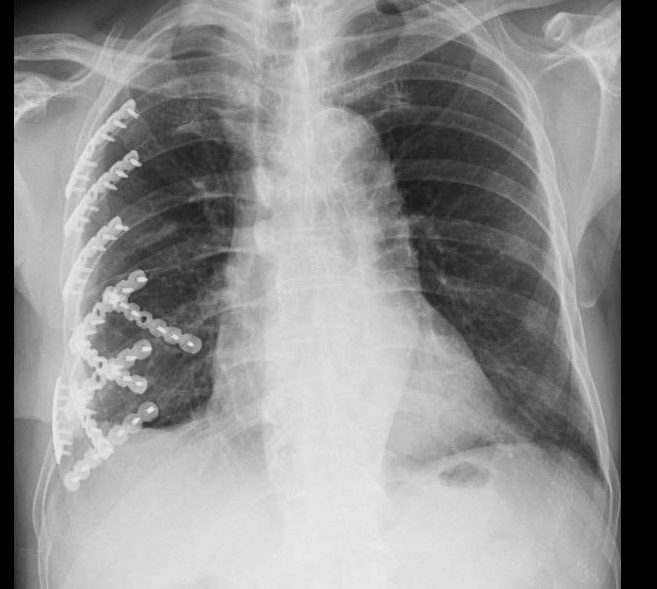

▲ 老翁在胸腔創傷微創重建中心進行微創肋骨手術,固定9根肋骨及重建胸廓(圖/彰化醫院提供)

林聿騰說,王老先生右胸肋骨有9根斷裂,並不是只有1根,有的斷裂處可能是車禍之後才顯現。在王老先生止住出血點之後1週,在胸腔創傷微創重建中心進行微創肋骨手術,固定9根肋骨及重建胸廓。